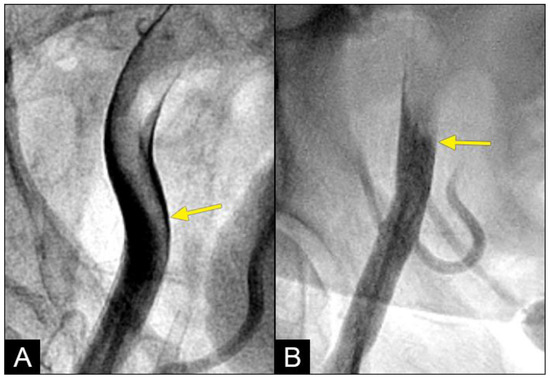

At the interface site, there were multiple levels of clashes depending on the level of blood pressure (BP). In cases of both severe systolic and diastolic hypertension (with systolic blood pressure (BP) > 160 mmHg and diastolic BP > 90 mmHg), the interface displayed a flat demarcation line, indicating a strong interaction between uncontrolled diastolic BP (DBP) and systolic BP (SBP) (Figure 7A). In cases of controlled SBP and elevated DBP, the interface appeared with a round proximal head (Figure 7B). In cases where diastolic BP was well controlled (<80 mmHg), there was no retrograde flow.

Figure 7.

(A,B) Interface of the collision between the antegrade blood flow and the retrograde contrast flow. The antegrade flow represents the systolic contraction, while the diastolic contrast flow represents the exaggerated peripheral vascular resistance or diastolic blood pressure (DBP). In patient (A), the systolic BP at the time of the iliac angiogram was 185/100 mmHg, while in patient (B), it was 120/90 mmHg.

COLLISION: In the iliac artery, near the end of systole and during the first half of diastole, the retrograde flow was observed moving upwards with a well-defined round head, despite the distinct separation between the two flows (Figure 8A,B). This retrograde flow was not laminar due to the heterogeneous composition of the fluid. There was a slight mixing of white blood and black contrast, with most of the fluid at the proximal head of the retrograde flow appearing predominantly black. The retrograde flow continued upwards (arrow) until it was overridden by the antegrade flow of the subsequent systole (Figure 8C,D). Overall, the interface between the antegrade and retrograde flows exhibited a subtle demarcation line, indicating a gentle interaction between the two opposing forces.

Figure 8.

(A–D) Interface of the collision between the antegrade blood flow and the retrograde contrast flow. These figures are in consecutive sequence. The antegrade flow represents the systolic contraction, while the diastolic contrast flow represents the exaggerated peripheral vascular resistance. (A) The blood advances with a soft, vague tip (yellow arrow). (B) Then, 0.067 s later, the retrograde flow begins to form, slowly pushing upwards (red arrow). (C–E) At the same time, the antegrade flow moves forward slowly (yellow arrow). At the interface, the proximal end of the retrograde flow has a round curve shape suggestive of a soft interaction with the antegrade flow (red arrow). The blood in white still flows forward at a slower pace (yellow arrow), while the retrograde flow moves upwards (red arrow).